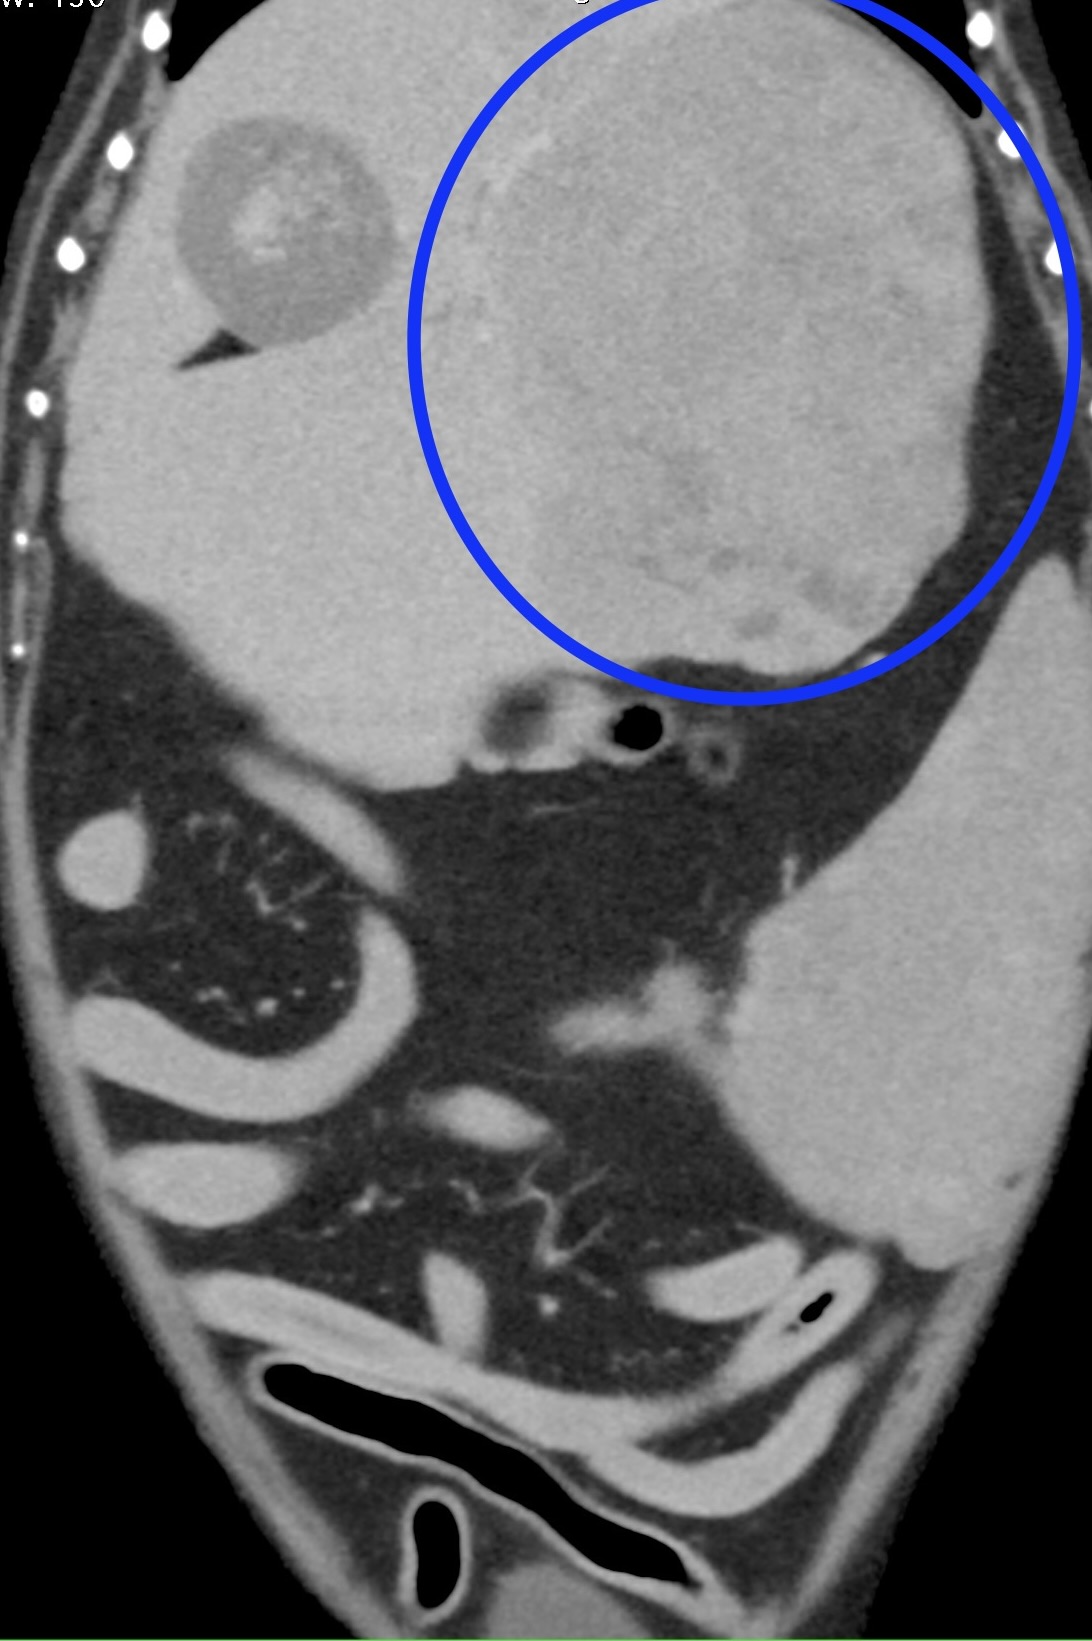

CT所見です。肝臓の左側に大きな塊状病変が認められます。